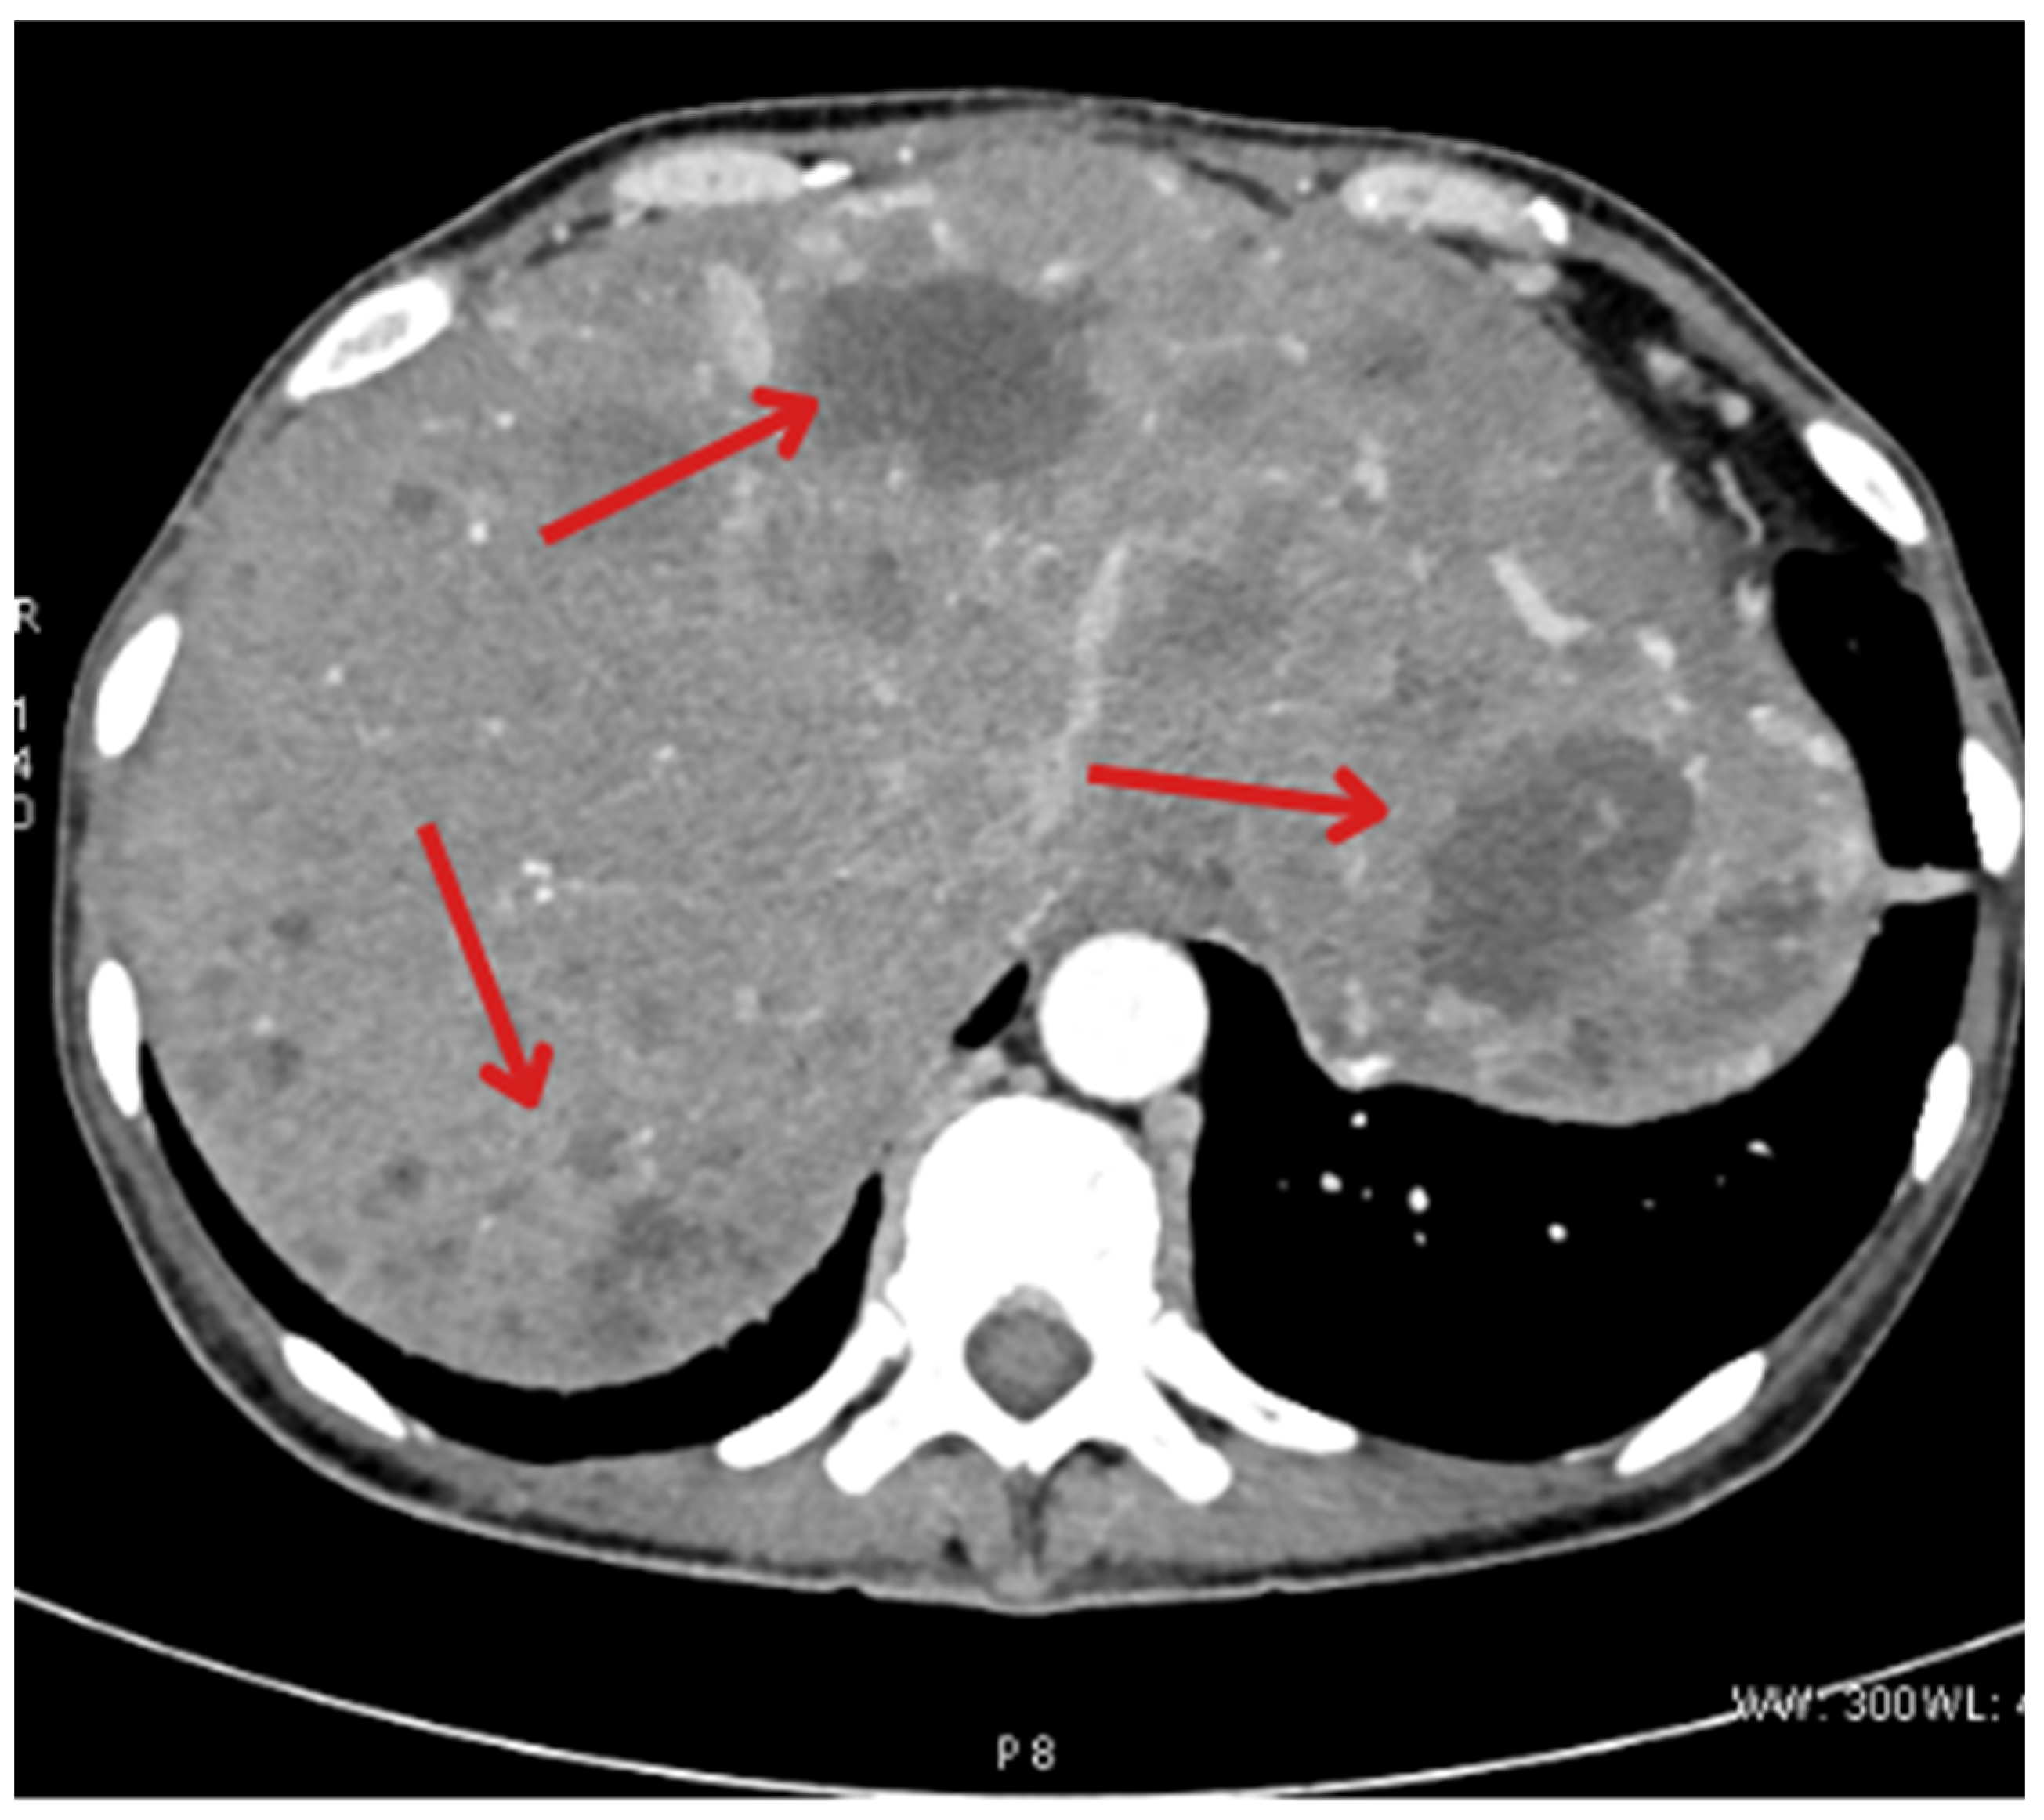

| November 2022 | Follow-up CT showing new metastases in S2, S3, and S6 of the liver |

| January 2023 | Follow-up PET showing foci in the liver, head of the pancreas, bones, and cervical lymph nodes |

| May 2023 | Beginning of Lutathera treatment CT scan: metastases in the liver, bone sclerosis, enlarged lymph nodes |